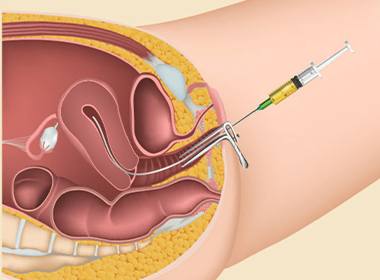

Intrauterine Insemination (IUI)

Placement of processed sperm directly into the uterus to increase chances of fertilization during ovulation.